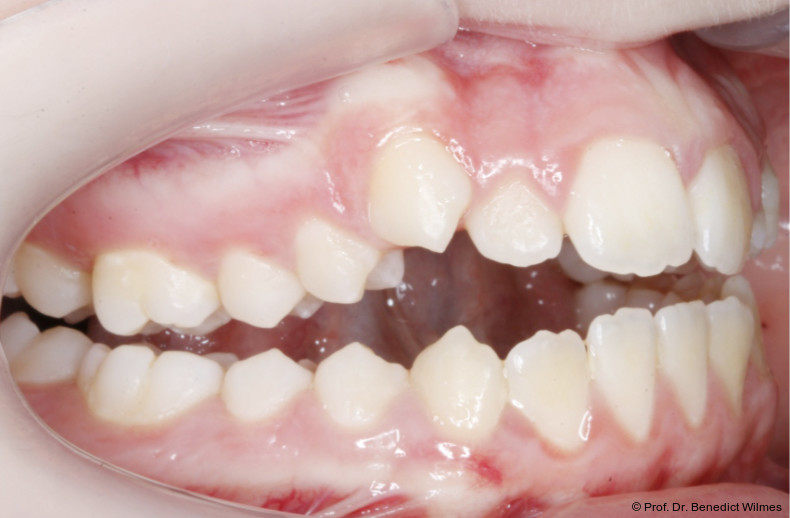

Eine 13-jährige Patientin stellte sich mit beidseitigem Kreuzbiss, einem anterioren offenen Biss und einer Angle Klasse II vor. Das viszerale Schluckmuster wurde mittels logopädischer Maßnahmen umgestellt, der offene Biss persistierte jedoch (Abb. 3a–l).